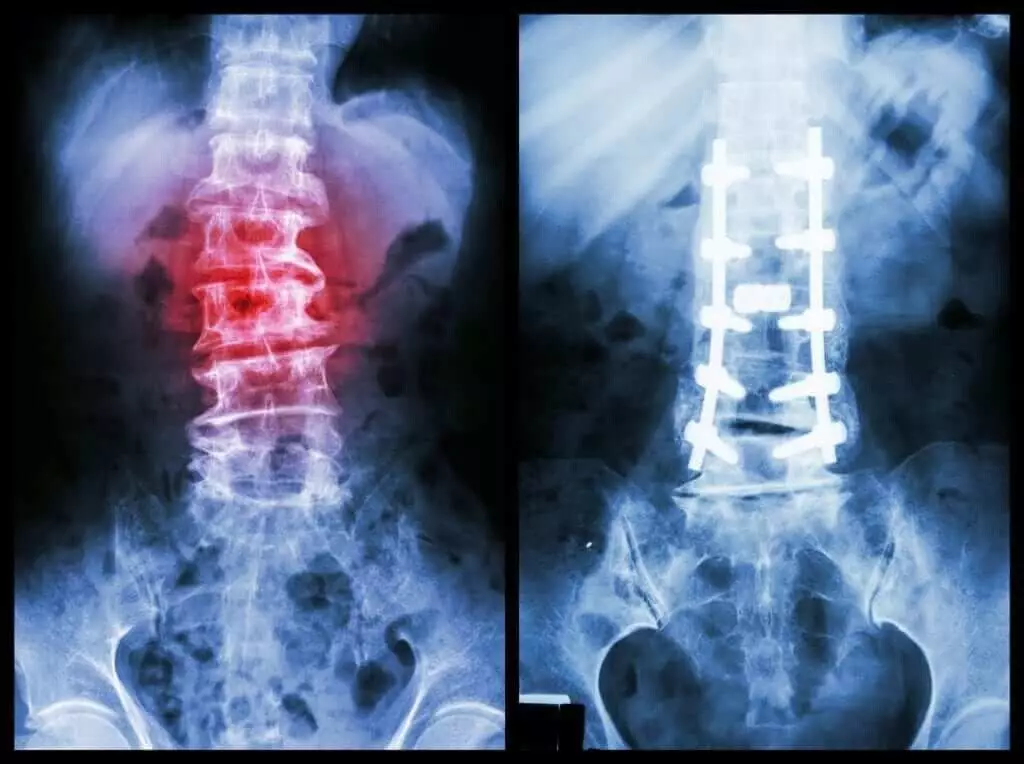

عملهای جراحی در تنگی کانال نخاعی

هنگامی که شدت تنگی کانال نخاعی بالا باشد و سایر شیوههای غیر جراحی نتوانند بهبودی لازم را حاصل کنند، عمل جراحی گزینه بعدی خواهد بود. این اعمال معمولاً شامل برداشتن بخشهایی از بافت استخوانی، خارهای استخوانی یا دیسکهایی هستند که فضای کانال نخاع را پر کرده و بر عصبهای نخاعی فشار میآورند.

از جمله روشهای جراحی تنگی کانال نخاعی میتوان به موارد زیر اشاره کرد:

- لامینکتومی: طی این عمل، بخشی از استخوان لامینا که درگیر آسیب است، برداشته میشود تا فضای اضافهتری در محدوده عصبها به وجود آید. در برخی موارد برای ایجاد ثبات، لازم است استخوان جداشده به استخوانهای مجاور پیوند زده شود.

- لامینوتومی: در این روش صرفاً قسمتی از لامینا برداشته میشود. جراح با ایجاد حفرهای بهاندازه مورد نیاز، فشار وارده به نقطه خاصی را رفع خواهد کرد.

- لامینوپلاستی: این تکنیک مخصوص مهرههای گردنی است. در این عمل، جراح با تعبیه لولایی روی لامینا، فضای کانال نخاعی را گسترش میدهد. سپس یک ابزار فلزی برای باز نگه داشتن آن قسمت استفاده میشود.

عموماً انجام چنین جراحیهایی در کاهش علائم مؤثر است، اما در پارهای از بیماران، ممکن است نشانهها تغییری نکند یا حتی تشدید شود. از عوارض بالقوه عمل جراحی میتوان به احتمال عفونت، ایجاد لخته خون در رگهای پا و پارگی غشای پوشاننده نخاع اشاره کرد.